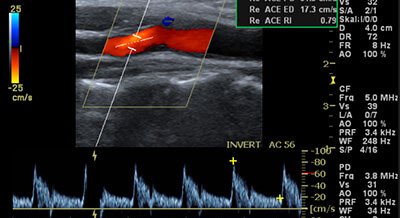

Mit dieser Untersuchung werden die Halsgefäße (Carotiden) mittels Ultraschall bildlich dargestellt. Dadurch können Ablagerungen (Plaques) oder Engstellen (Stenosen) frühzeitig erkannt werden, bevor es zu Durchblutungsstörungen oder Schlaganfall kommt.

Die Untersuchung ist schmerzfrei, ohne Strahlenbelastung und dauert nur wenige Minuten. Sie hilft, Ihr individuelles Risiko für Gefäßerkrankungen rechtzeitig einzuschätzen und gegebenenfalls vorbeugend zu handeln.